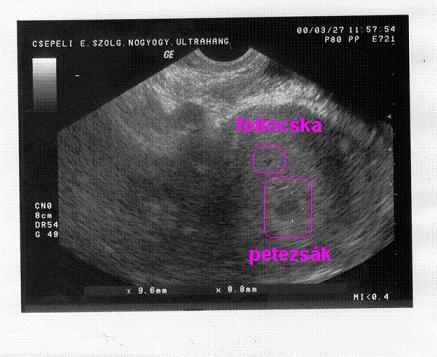

2008.03.28 11:36

2008.03.28 16:56